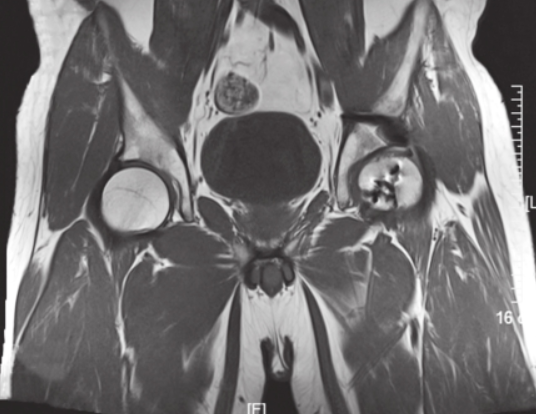

术后头孢唑啉预防感染2天,体温正常,各项感染指标无异常。术后第7天出院。分别于术后8周、6个月、12个月复查X线片(图8),术后6个月的X线片见股骨头及髋臼后壁骨折均已愈合。术后12个月随访时患者髋关节功能良好,无疼痛,MRI见股骨头骨折愈合良好,无坏死(图9)。

图9 术后MRI检查